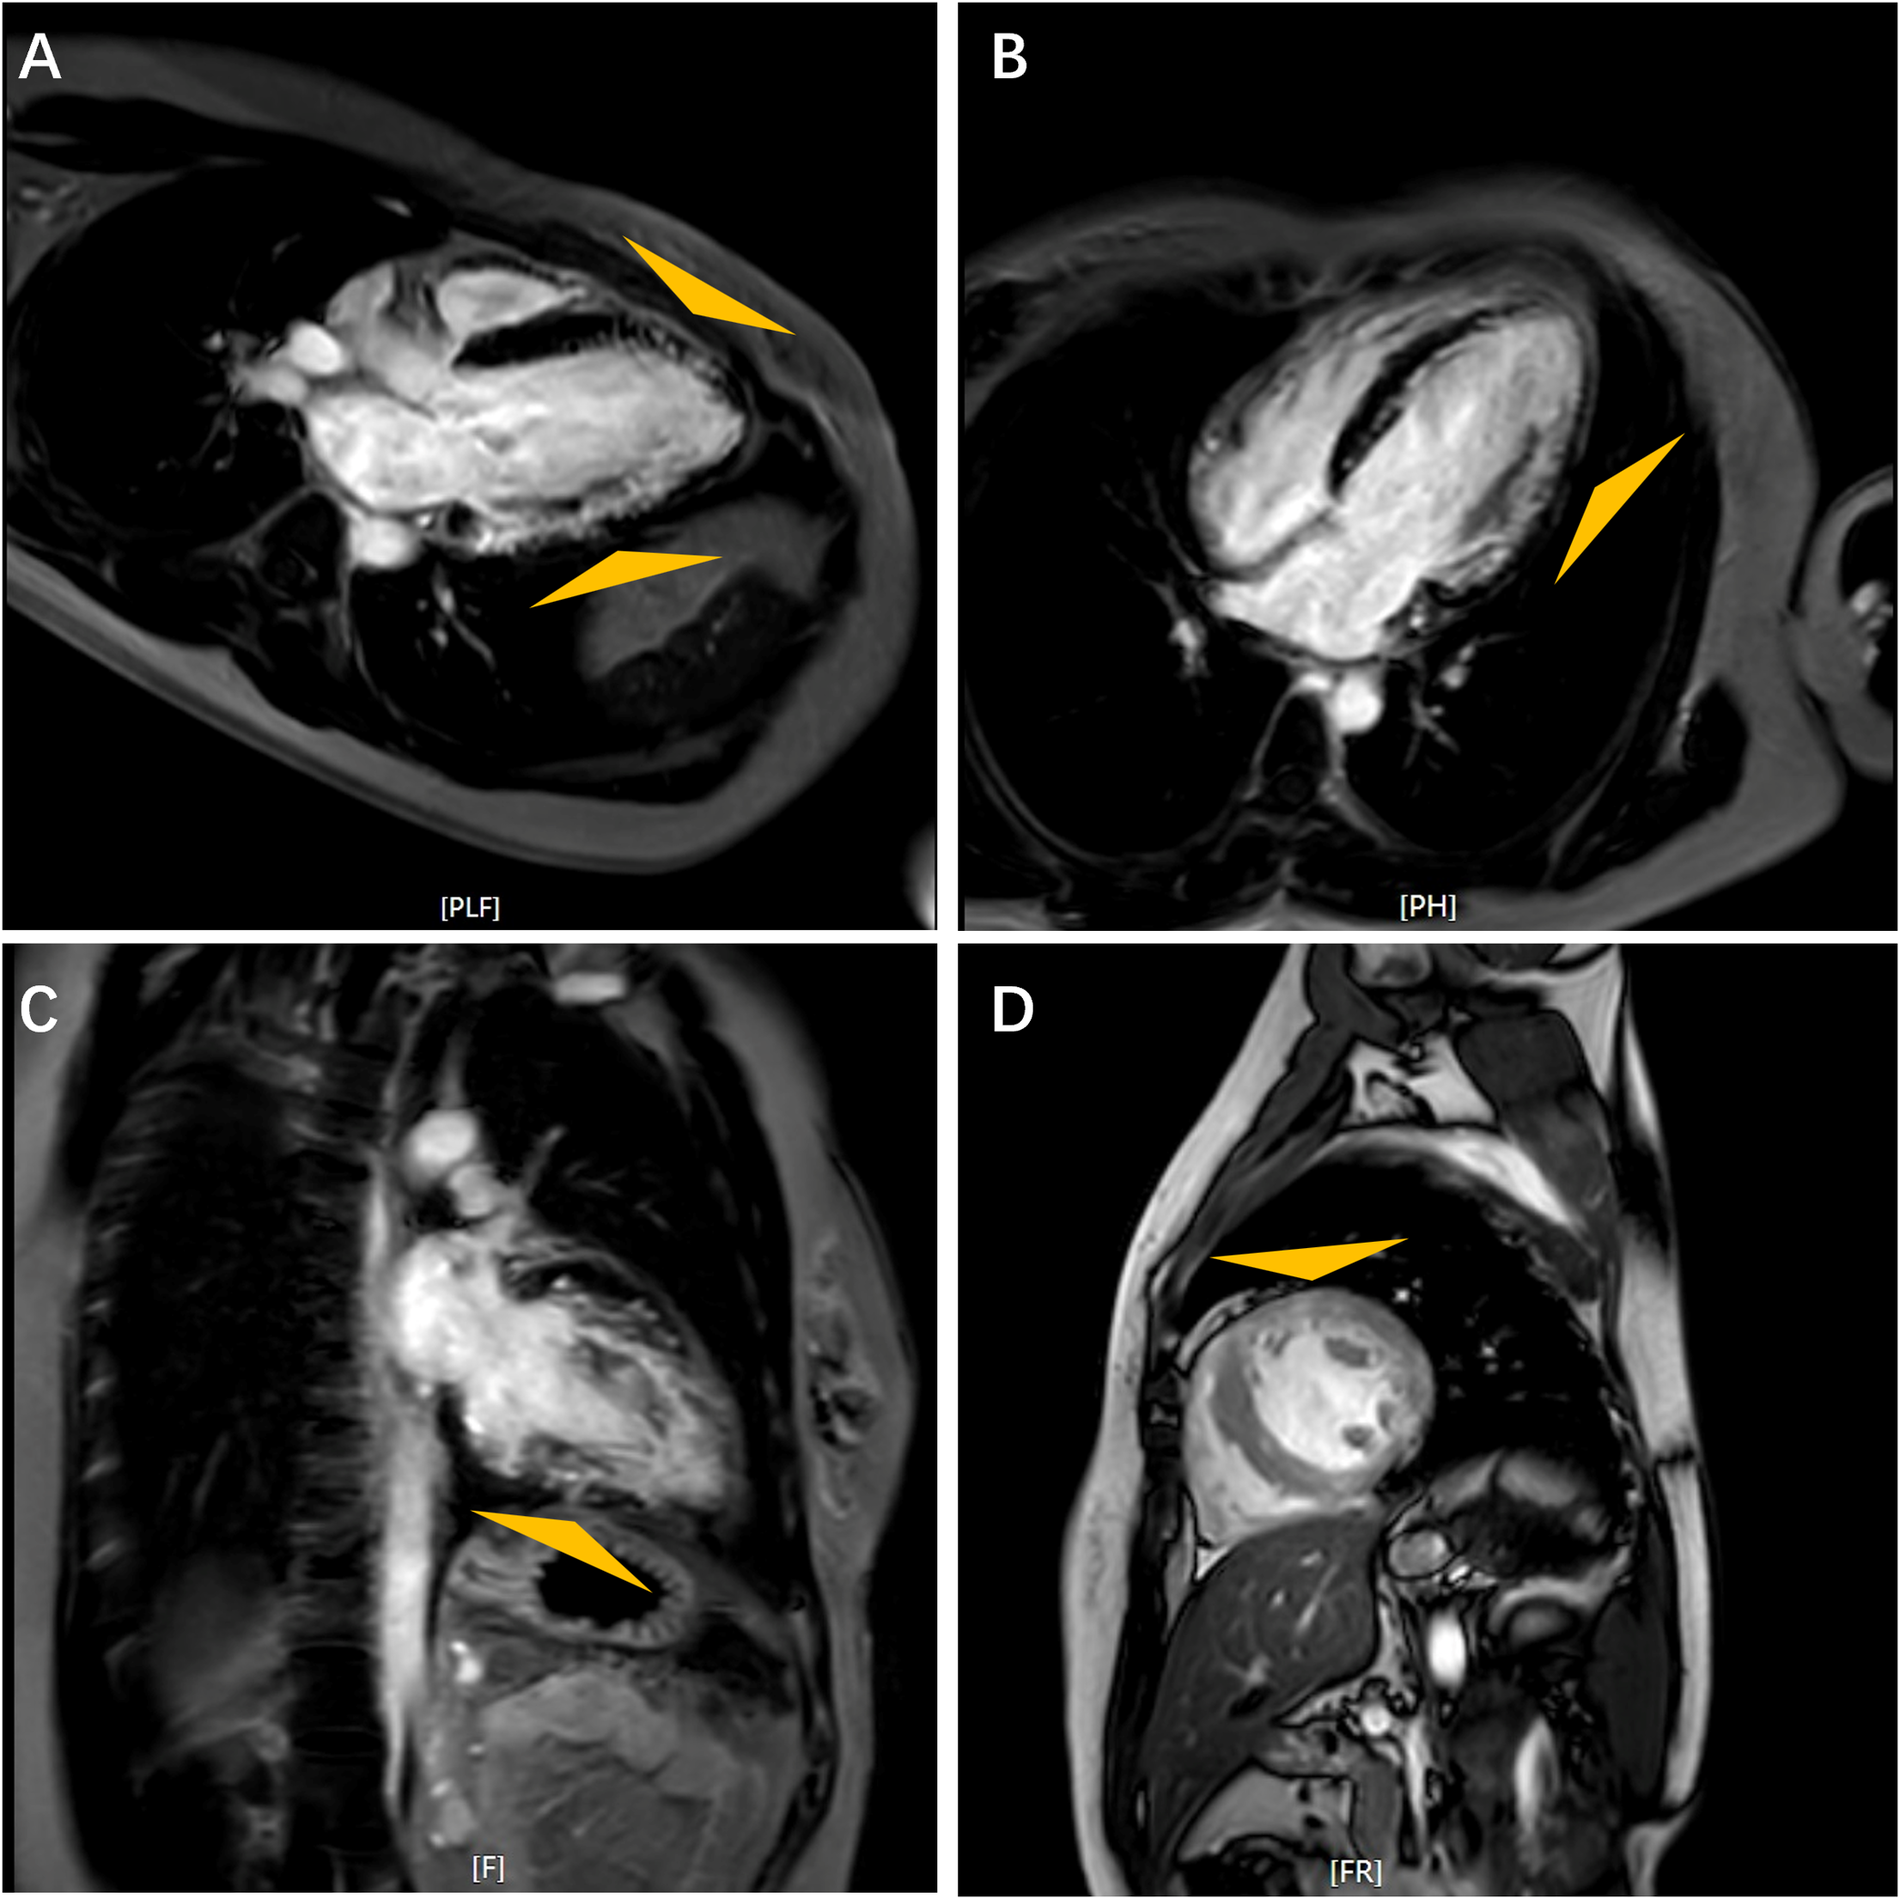

On admission, the patient's vital signs were within normal range, and she demonstrated no clinical sign of heart failure. Laboratory findings are detailed in Supplementary Table S1. Electrocardiogram (EKG) revealed a short PR interval of 106 ms, ventricular pre-excitation and sinus rhythm with a heart rate of 67 beats per minute (Supplementary Figure S2). ECG indicated mild left ventricular hypertrophy with thickness of 12 mm in interventricular septum and posterior wall, and impaired systolic function with an estimated LVEF of approximately 48% (Supplementary Figure S3). Further evaluation with cardiac magnetic resonance (CMR) imaging revealed diminished left ventricular wall contraction and late gadolinium enhancement (LGE) involving the subendocardium (indicated by triangles in Figure 1).

Figure 1

Cardiac magnetic resonance images. Feather-like delayed gadolinium enhancement in the left ventricular wall as indicated by triangles. Long Axis (A); Horizontal Long Axis (B); Four-Chamber View (C); Short Axis (D).